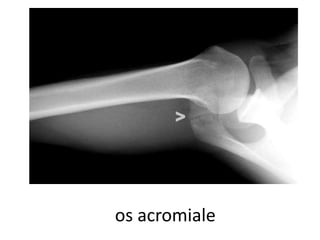

Associated conditionshook-shaped acromion

• os acromiale

os acromiale